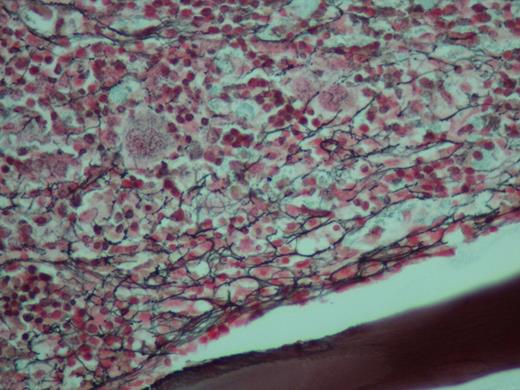

Reticulin stain of biopsy showing a moderate to marked increase in coarse reticulin fibers

A bone marrow biopsy was performed which showed a hypercellular marrow, with absence of myeloid precursors and decrease in erythroid cells. The predominant components were atypical megakaryocytes, plasma cells and eosinophils Reticulin stain showed marked increase in coarse reticulin. Occasional large histiocytes were visualized with engulfed lymphocytes, polymorphonuclear and red blood cells. Flow cytometry was negative for a myeloproliferative disorder.